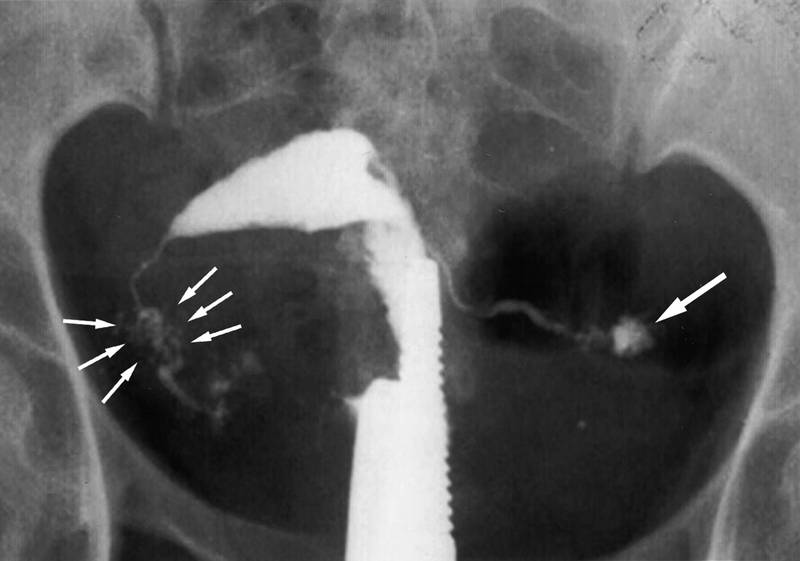

Медицинские снимки: Проходимость маточных труб

Раздел: Кадры-подсказки